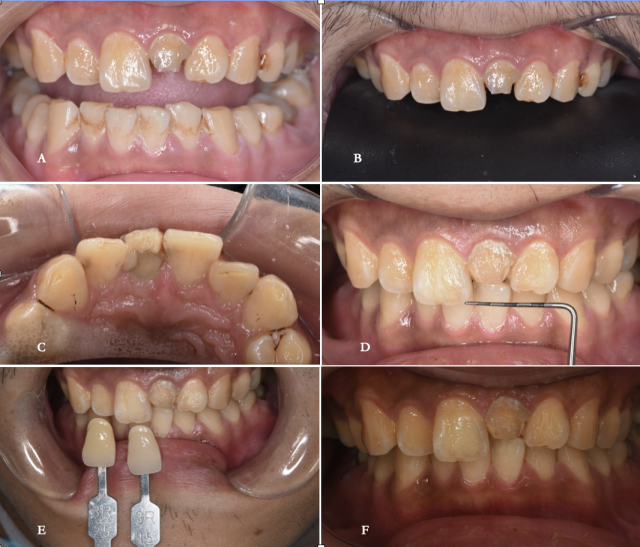

术前口内照片 A.术前唇面照;B.术前黑背板照;C.术前舌侧照;D.术前牙齿宽度测量;E.牙周基础治疗后的比色照;F.偏振光照看牙齿纹理